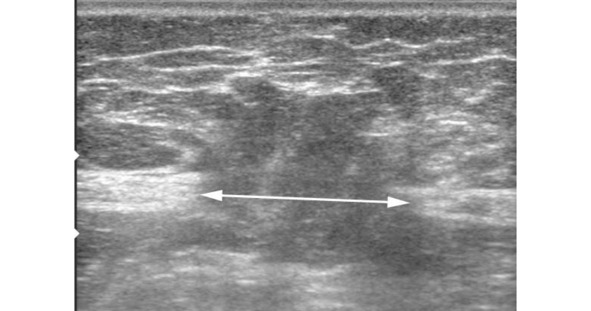

Полученные данные при ультразвуковом исследовании передней брюшной стенки и органов брюшной полости позволяют: оценить состояние мышечно-апоневротических структур; определить ширину основного грыжевого дефекта (рис. 32), наличие или отсутствие дополнительных грыжевых отверстий; выявить симультанную хирургическую патологию органов брюшной полости; определить характер спаечного процесса и выраженность явлений частичной кишечной непроходимости; выявить очаги хронического воспаления. Однако при больших грыжах информативность УЗИ значительно снижается, в связи с чем для получения более точной информации по всем параметрам грыж необходимо проведение рентгеновской компьютерной томографии.

Рис. 32 Эхограмма передней брюшной стенки у больной с послеоперационной грыжей средней линии живота M2W1. Прямой линией со стрелками на концах отмечены грыжевые ворота